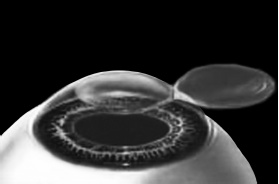

После формирования роговичного лоскута убирают инструменты микрокератома, затем шпателем откидывают его вбок (рис. 5). Обнажается роговичное ложе, то есть место, на котором лежал лоскут. Это верхние слои стромы роговицы. Ложе осушают тупфером и так же, как и при ФРК, настраивают лазер и испаряют несколько микрон вещества стромы (рис. 6). Потом промывают строму водой и шпателем укладывают лоскут на место.

Рис. 5. Роговичный лоскут откинут в сторону.

Иллюстрация с сайта Международного лазерного центра www.optics.ru